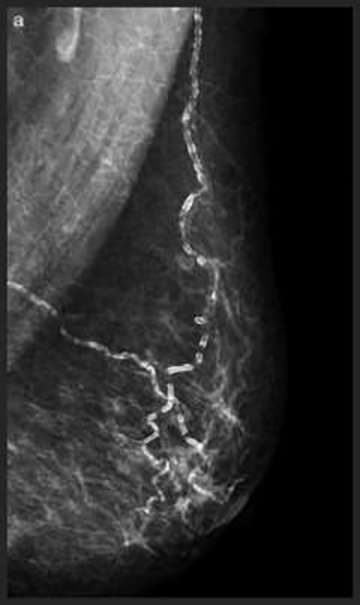

![]() Large Rod-like Calcifications: thick calcifications which follow the ducts, toward the nipple, secondary to secretory disease